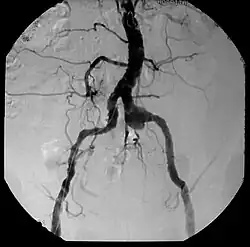

| Aneurysm, a commonly lethal complication of SA | |

Syphilitic aortitis is inflammation of the aorta associated with the tertiary stage of syphilis infection. SA begins as inflammation of the outermost layer of the blood vessel, including the blood vessels that supply the aorta itself with blood, the vasa vasorum.[3] As SA worsens, the vasa vasorum undergo hyperplastic thickening of their walls thereby restricting blood flow and causing ischemia of the outer two-thirds of the aortic wall. Starved for oxygen and nutrients, elastic fibers become patchy and smooth muscle cells die. If the disease progresses, syphilitic aortitis leads to an aortic aneurysm. Overall, tertiary syphilis is a rare cause of aortic aneurysms.[3] Syphilitic aortitis has become rare in the developed world with the advent of penicillin treatments after World War II.

Inflammatory involvement of tertiary syphilis begins at the adventitia of the aortic arch which progressively causes obliterative endarteritis of the vasa vasorum.[3] This leads to narrowing of the lumen of the vasa vasorum, causing ischemic injury of the medial aortic arch and then finally loss of elastic support and dilation of the vessel.[3] Dissection of the aortic arch is rare due to medial scarring. As a result of this advanced disease process, normal methods of angiography/angioplasty may be impossible for those with suspected coronary artery disease.